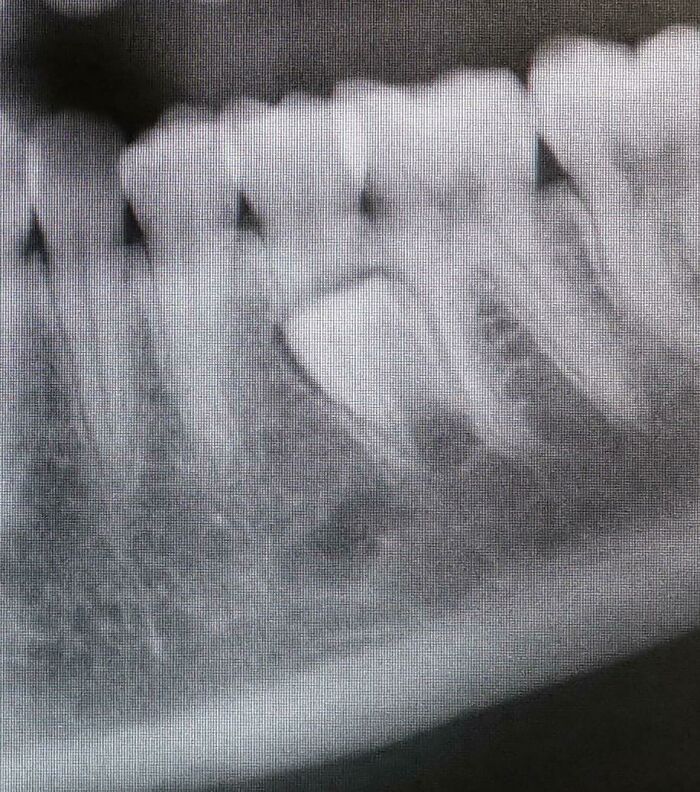

My Tooth Has Really Long Roots